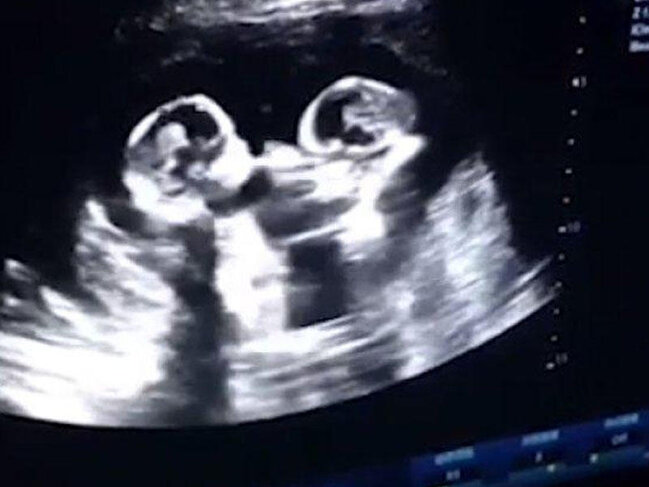

7News.Az xəbər verir ki, ultrasəs müayinə əkiz körpələrin hələ ana bətnində olarkən bir-biri ilə yumruqlaşdığını ortaya çıxarıb.

Körpələr bu müayinədən dörd ay sonra sağlam şəkildə dünyaya gəliblər. Bacılardan birinin çəkisi təxminən 1,6, digərinin çəkisi isə 1,95 kiloqram olub.

Amma məsələ burasındadır ki, əkiz və ya üçəm körpələr ana bətnində ayrı-ayrı döllərdə inkişaf etdiyi halda, sözügedən hamiləlikdə əkizlər eyni döldə olub. Həkimlərin sözlərinə görə, bu 30 milyonda bir qeydə alınan haldır. (publika.az)